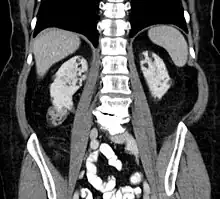

Computed tomography showing multiple angiomyolipomas of the kidney in a patient with lung lymphangioleiomyomatosis on CT: suspected TSC

Between 26% and 80% of TSC patients have benign tumors of the kidneys called angiomyolipomas, with hematuria being the most frequent presenting symptom. [9] TSC angiomyolipomas differ from non-TSC angiomyolipomas in age of presentation (31.5 years vs 53.6 years), mean tumor size (8.2 cm vs 4.5 cm), and percentage of cases requiring surgical intervention (50% vs 28%).[9] Although benign, an angiomyolipoma larger than 4 cm is at risk for a potentially catastrophic hemorrhage, either spontaneously or with minimal trauma.